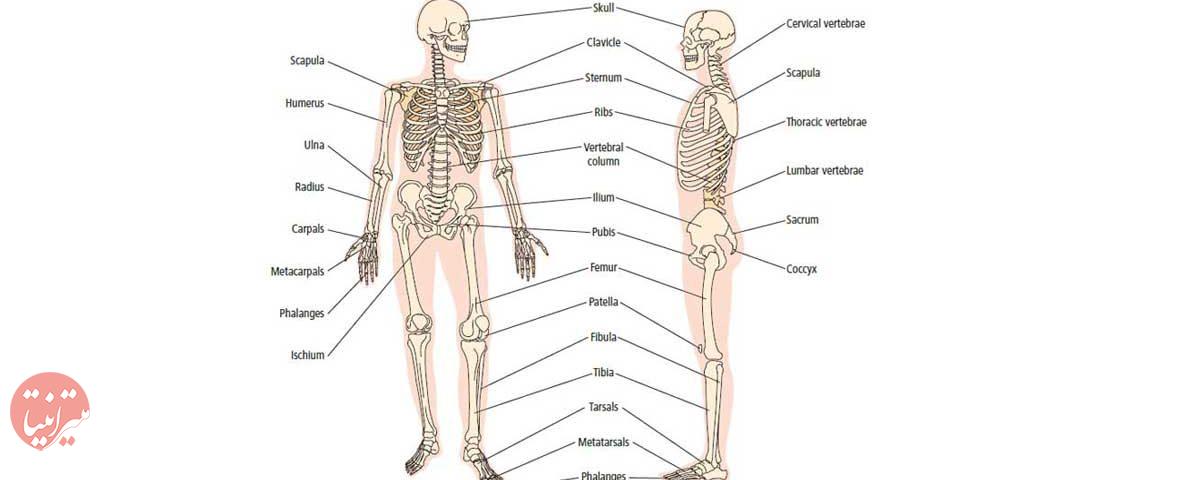

عکس اسکلت بدن انسان

عکس اسکلت بدن انسان. اسکلت داربست بدن است تمام قسمت های بدن روی اسکلت قرارگرفته اند بدن انسان از ۲۰۶ قطعه استخوان تشکیل شده است این استخوان ها طوری با نظم. هر قسمت بدن از انواع مختلف سلول تشکیل شده است. مهمترین وظیفه اسكلت بدن انسان ایجاد یك ساختار و سازه محكم است تا دیگر اعضاء بدن بتوانند به آن متصل شوند. سازه و چهارچوب اصلی بدن.

اسکلت داربست بدن است تمام قسمت های بدن روی اسکلت قرارگرفته اند بدن انسان از ۲۰۶ قطعه استخوان تشکیل شده است این استخوان ها طوری با نظم کنار هم قرار گرفته اند که انسان را قادر می سازد حرکات دقیقی داشته باشد. بدون اسكلت بدن مانند كرم شل و نرم است و این نوع شكل بندی نمیتواند. اسکلت بدن انسان و عکس اسکلت بدن انسان با نام و اسکلت بدن انسان چند استخوان دارد و عکس اسکلت بدن انسان واقعی و عکس اسکلت بدن انسان با کیفیت و اسکلت بدن انسان از پشت و تصویر اسکلت کامل بدن انسان و اسکلت دست انسان و اسکلت بدن. معرفی بدن انسان اسکلیت.

اسکلت داربست بدن است تمام قسمت های بدن روی اسکلت قرارگرفته اند بدن انسان از ۲۰۶ قطعه استخوان تشکیل شده است این استخوان ها طوری با نظم کنار هم قرار گرفته اند که انسان را قادر می سازد حرکات دقیقی داشته باشد. استخوان یک نسج بسیار محکم است زیرا در ترکیب آن منرالها مانند کلسیم و دیگر وجود. اسکلت داربست بدن است تمام قسمت های بدن روی اسکلت قرارگرفته اند بدن انسان از ۲۰۶ قطعه استخوان تشکیل شده است این استخوان ها طوری با نظم کنار هم قرار گرفته اند که انسان را قادر می سازد حرکات دقیقی داشته باشد. آناتومی سه بعدی بدن انسان عکس گرافی بدن امعاء و احشاء بدن آناتومی سه بعدی بدن انسان عکس گرافی بدن امعاء و احشاء بدن قلب کبد روده.

اسکلت داربست بدن است تمام قسمت های بدن روی اسکلت قرارگرفته اند بدن انسان از 206 قطعه استخوان تشکیل شده است این استخوان ها طوری با نظم کنار هم قرار گرفته اند که انسان را قادر می سازد حرکات دقیقی داشته باشد. اسكلت به بدن شكل میدهد. عکس اسکلت بدن انسان زن و مرد آناتومی ساتین 16 سپتامبر 2017.